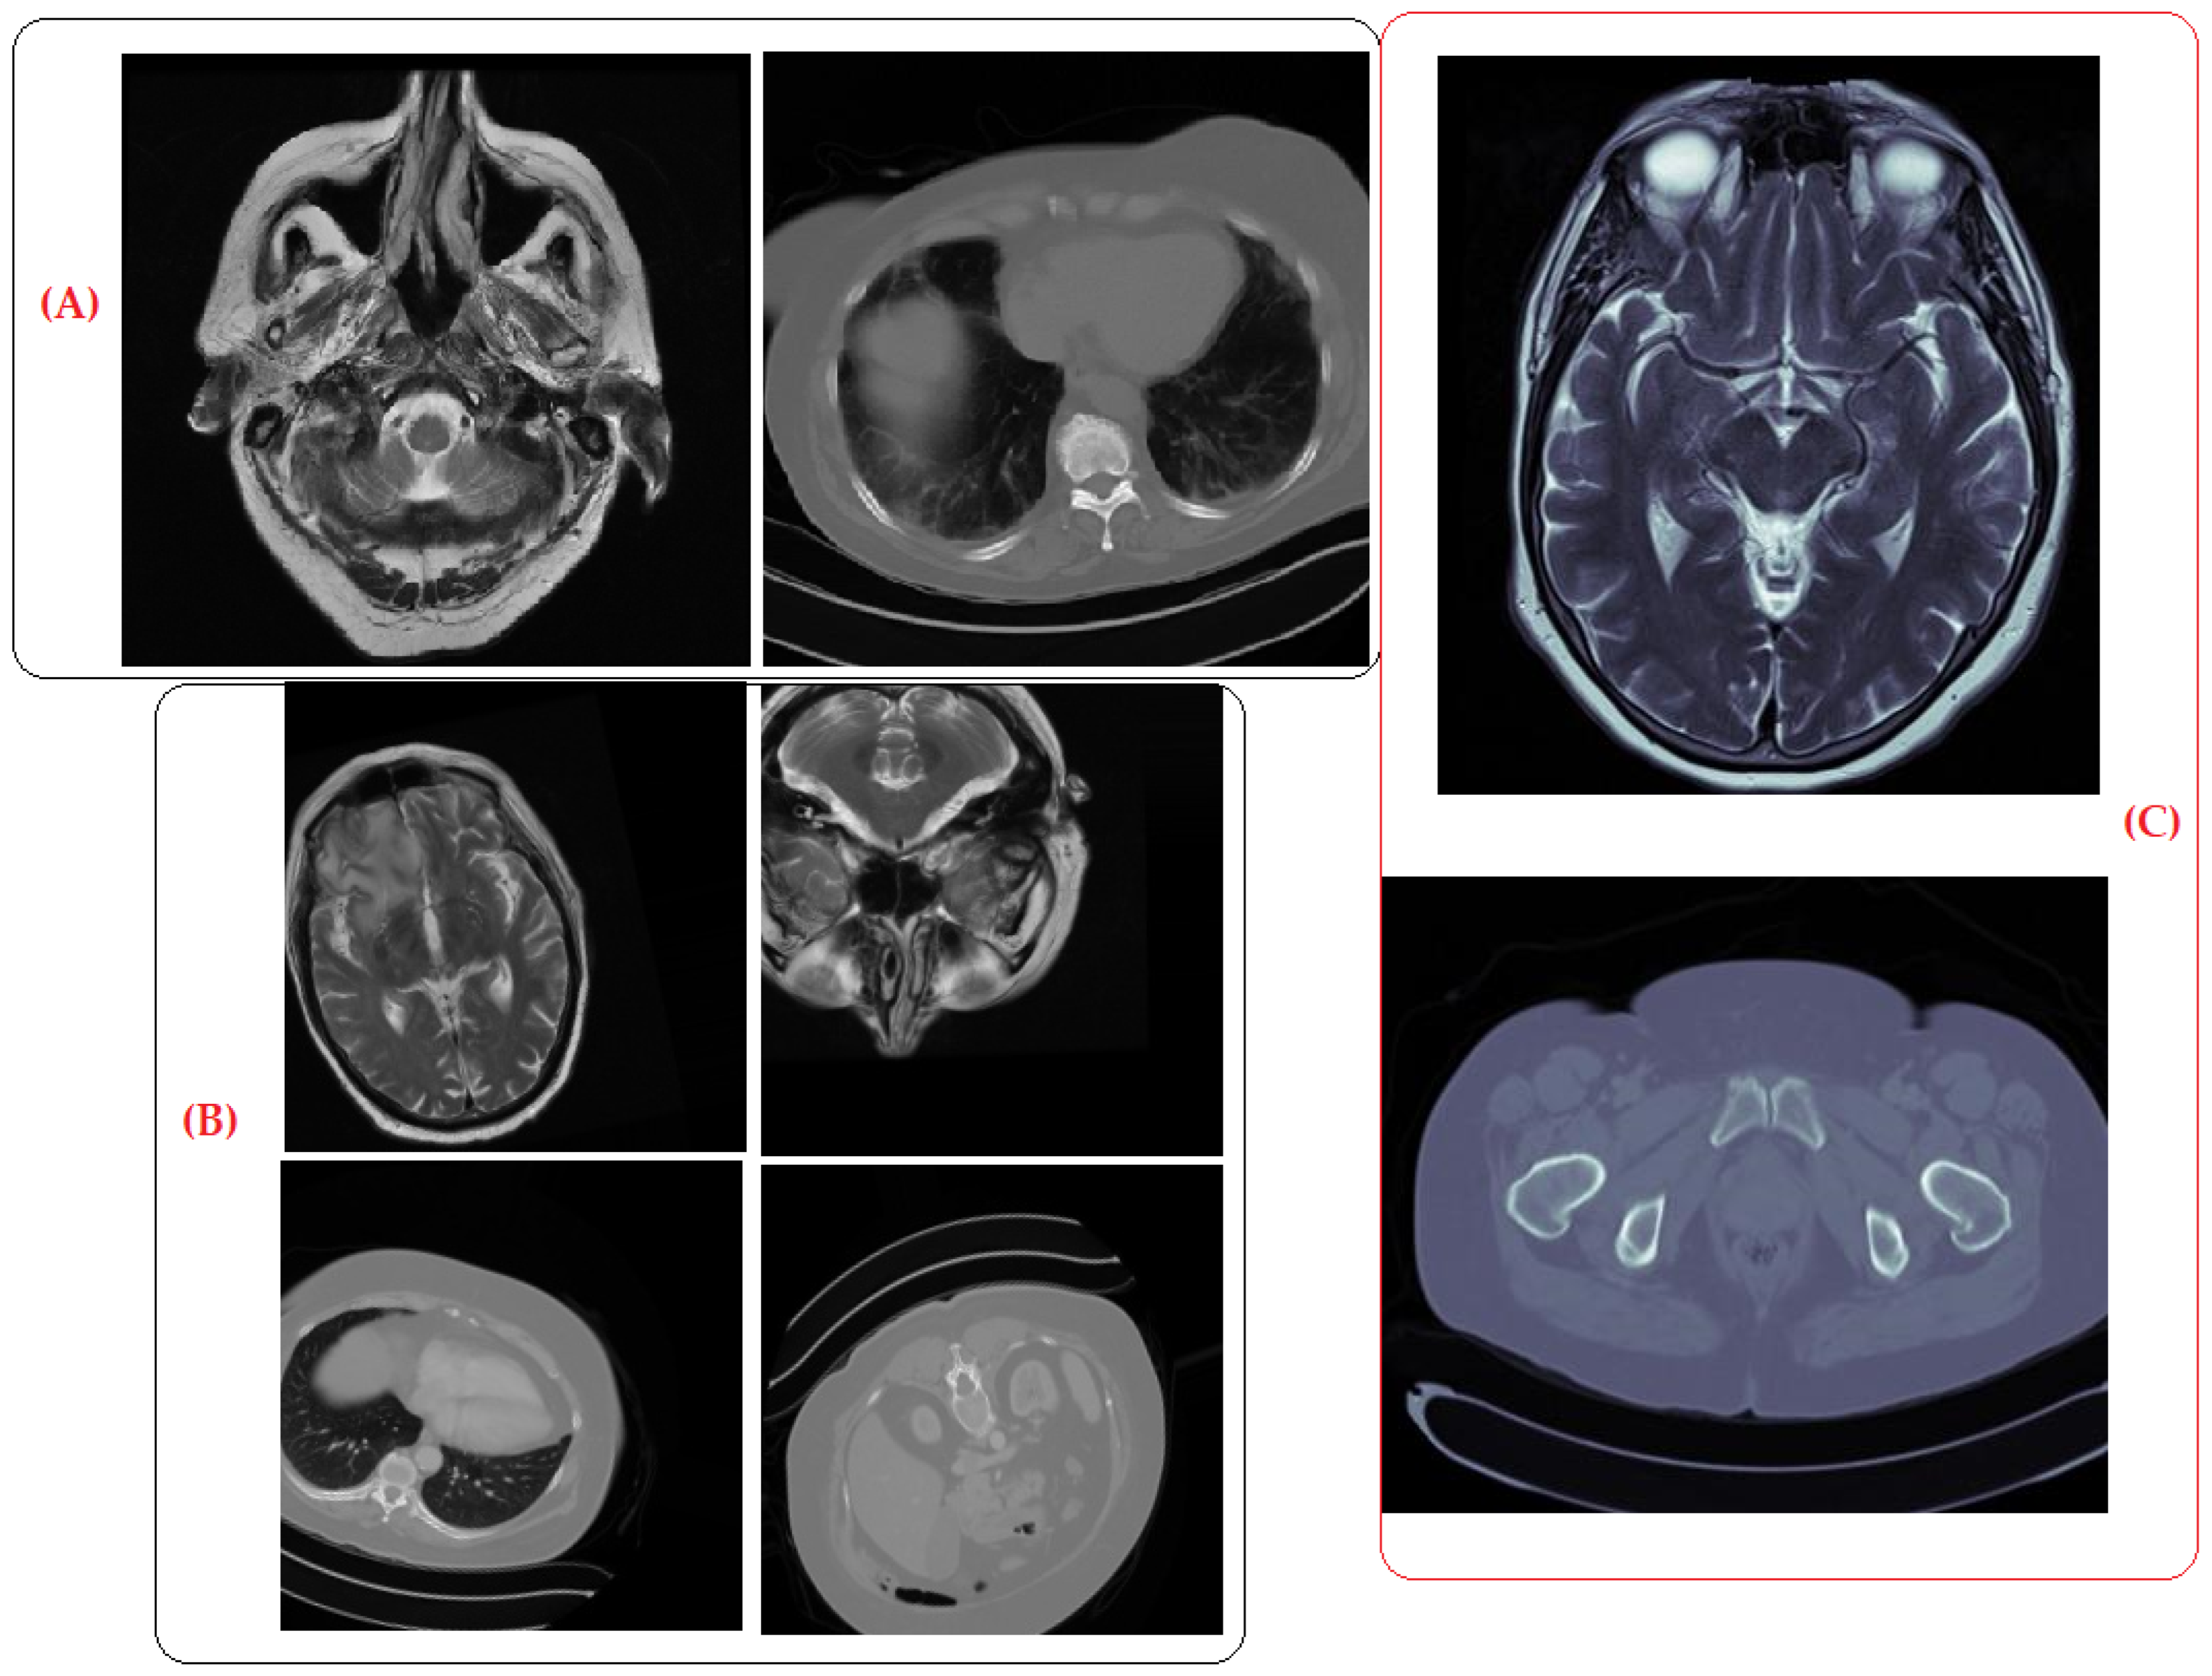

Sample Images: To provide further clarity on the quality of the synthetic images, we include sample images in Figure 10.

Figure 10.

(A) Original, (B) augmented, and (C) synthetic images generated by DCGAN.

The comparable performance of the radiologists in categorizing real, augmented, and generated images confirmed the efficacy of the DCGAN in producing realistic synthetic images. The DCGAN not only generated new images but also provided notable benefits, such as the ability to generate synthetic images with diverse variations, enhance image qualities, and streamline the training process by eliminating artifacts. These images can be confidently used for training machine learning models, enhancing the diversity and robustness of the datasets to enhance the accuracy of model performance.